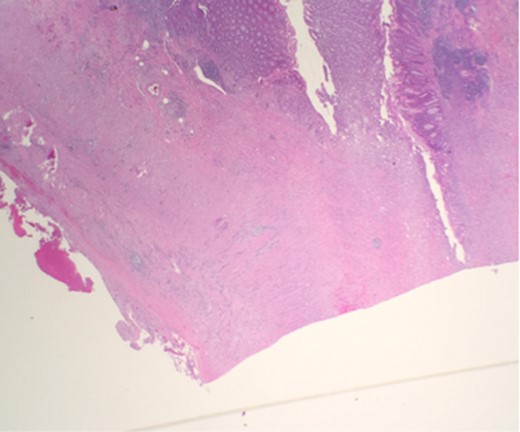

Microscopic examination reveals thickened appendicial wall with infiltrating individual malignant cells (Fig. 1).

Microscopic examination reveals thickened appendicial wall with infiltrating individual malignant cells.